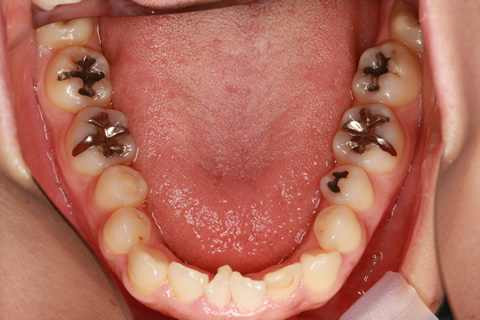

受け口(反対咬合)の症例

症例一覧